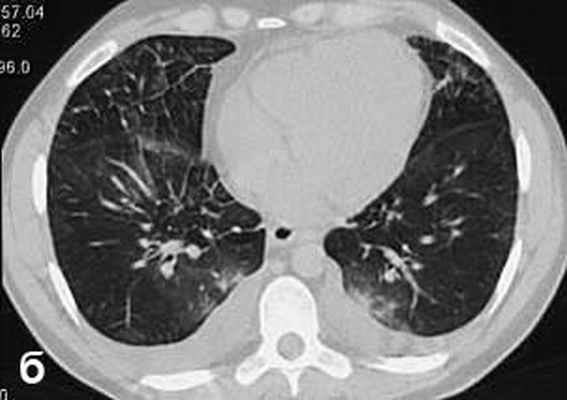

В течение недели прошла одышка, уменьшилась тахикардия, над легкими перестали выслушиваться хрипы, подверглись обратному развитию проявления геморрагического васкулита и ливедо. Однократно проведена плевральная пункция с удалением 700 мл выпота соломенно-желтого цвета. При контрольной КТ органов грудной клетки через неделю лечения лимфаденопатия средостения и изменения легочной ткани по типу “мaтового стекла” не определялись (рис. 6). В стационаре прибавил в весе 5 кг. Клинический анализ крови нормализовался с марта 2007 г.

| Рис. 6. КТ через месяц лечения: отсутствуют изменения в средостении и легочной ткани | |